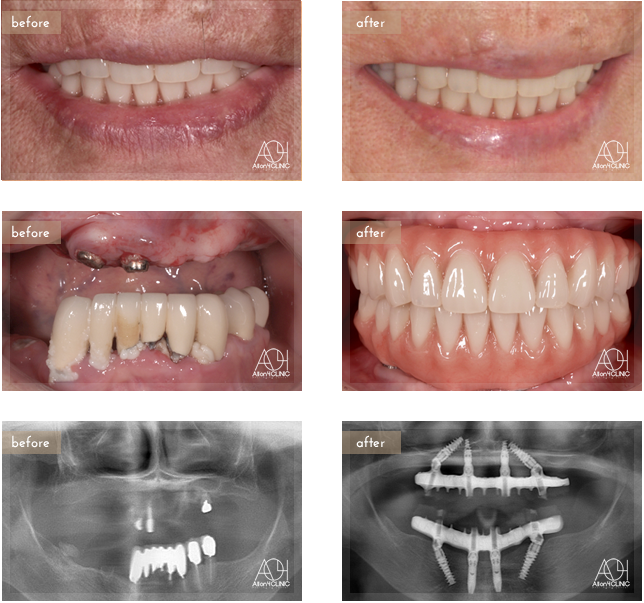

Age : 61

Sex : Female

Treatment :

- Maxilla All-on-4

- Under All-on-4

上顎は4本のNobel Activeインプラント、下顎は前方Nobel Active、後方Speedy groovyを埋入。上部構造はチタンPIBフレーム人工歯タイプ(歯肉:アクリリックレジン 歯:人工歯)